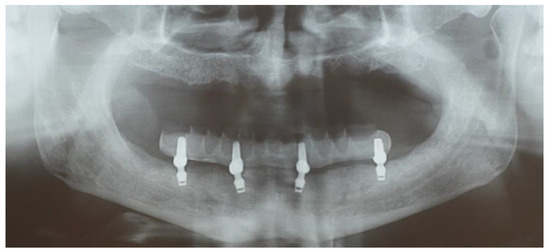

Edentulous Mandibles Restored with Fiber-Reinforced Composite Prostheses Supported by 5.0 mm Ultra-Short Implants: Ten-Year Follow-Up

2. Materials and Methods

3. Results

| MBL (mm) | Baseline | 0.18 (0.1–0.3, 0.08) | <0.001 | 0.12 (0.09; 0.15) | <0.001 | BL vs. 5 y |

| 5 years | 0.05 (−0.2–0.25, 0.1) | 0.09 (0.03; 0.15) | 0.02 | 5 y vs. 10 y | ||

| 10 years | −0.03 (−0.4–0.4, 0.21) | 0.21 (0.16; 0.27) | <0.001 | BL vs. 10 y | ||